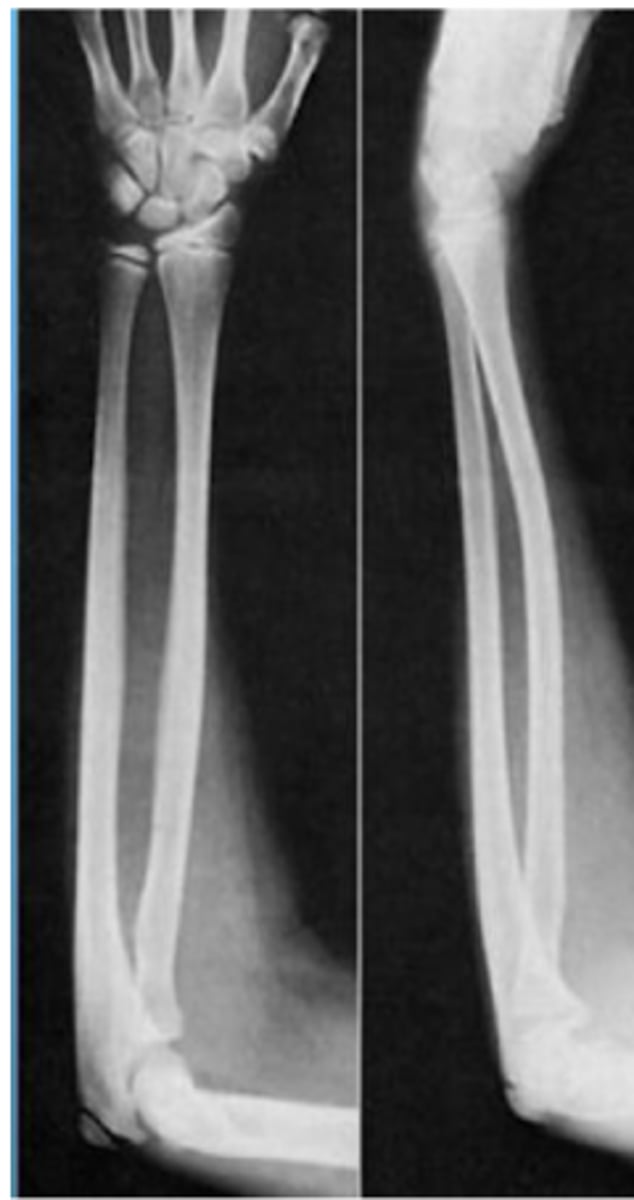

greenstick fracture

Incomplete break, causing bending of bone

torus fracture

- AKA: impacted, buckle

- Broken bone ends driven into one another

- Greenstick Fracture

- Epiphyseal (growth plate) fractures

- Plastic deformation

what types of fractures are more likely to be seen in children (3 types)